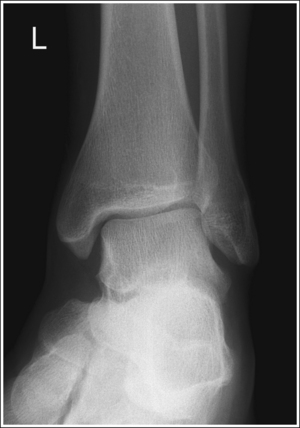

See Figure 6-55 and Box 6-12.

Contrast and density are adequate to demonstrate the anterior pretalar and posterior pericapsular fat pads on the foot and ankle.

• Fat pads on the ankle. Two soft tissue structures located around the ankle may indicate joint effusion and injury—the anterior pretalar fat pad and the posterior pericapsular fat pad. The anterior pretalar fat pad is demonstrated anterior to the ankle joint and rests next to the neck of the talus (Figure 6-56). The posterior fat pad, positioned within the indentation formed by the articulation of the posterior tibia and talar bones (see Figure 6-56), is displaced in the same manner as the anterior pretalar fat pad, although it is less sensitive and requires more fluid evasion to be displaced.

The ankle is in a lateral projection. The domes of the talus are superimposed, the tibiotalar joint is open, and the distal fibula is superimposed by the posterior half of the distal tibia.

• To obtain a lateral ankle projection, begin with the patient in a supine position, with the leg extended (Figure 6-57) and the foot dorsiflexed until its long axis forms a 90-degree angle with the lower leg. Rotate the patient and affected leg until the lateral foot surface is against the IR, and then adjust the degree of rotation until the surface is aligned parallel with the IR (Figure 6-58). For most patients, this positioning places the lower leg parallel with the imaging table. If this is not the case, as with a patient with a large upper thigh, the foot and IR should be elevated until the lower leg is parallel with the imaging table.

• Effect of lower leg positioning on talar dome superimposition. Often, if the knee is not fully extended (Figure 6-59) or if the distal tibia is not elevated to place the lower leg parallel with the IR in a patient with large upper thighs, the proximal tibia is positioned farther from the imaging table than the distal tibia. The resulting image demonstrates the lateral talar dome proximal to the medial talar dome and the height of the longitudinal arch appears less than it actually is because the cuboid shifts anteriorly and the navicular bone moves posteriorly in this position and the talocalcaneal joint will be narrowed (see Image 43). If the distal tibia is positioned farther from the table than the proximal tibia, the medial talar dome is demonstrated proximal to the lateral dome, and the height of the longitudinal arch appears greater than it actually is because the cuboid shifts posteriorly and the navicular bone moves anteriorly in this position and the talocalcaneal joint will be widened (see Image 44). When viewing a lateral ankle projection that demonstrates one of the talar domes proximal to the other, evaluate the height of the longitudinal arch and the degree of talocalcaneal joint visualization to determine which dome is the proximal dome. If the navicular bone is superimposed over more of the cuboid than expected and a narrowed talocalcaneal joint is seen, the lateral dome is the proximal dome. If the navicular bone is superimposed over less of the cuboid than expected and a wider talocalcaneal joint is seen, the medial dome is the proximal dome.

• Effect of foot positioning on talar dome superimposition. To demonstrate accurate AP alignment of the talar domes, position the lateral surface of the foot parallel with the IR. If this surface is not parallel with the IR, the talar domes are demonstrated one anterior to the other. When the leg is rotated more than needed to place the lateral foot surface parallel with the IR (leg externally rotated), as shown in Figure 6-60, the medial talar dome is demonstrated anterior to the lateral talar dome (see Image 45). If the leg is not rotated enough to place the lateral foot surface parallel with the IR (leg internally rotated), as shown in Figure 6-61, the medial talar dome is demonstrated posterior to the lateral talar dome (see Image 46). When taking a lateral ankle projection that demonstrates one of the talar domes anterior to the other, observe the position of the fibula in relation to the tibia to determine how the patient should be repositioned. On most lateral ankle projections with accurate positioning, the fibula is positioned in the posterior half of the tibia. On a lateral projection with poor positioning, if the fibula is demonstrated more posteriorly, the medial dome is anterior and the patient was positioned with the forefoot depressed and the heel elevated (leg externally rotated), as shown in Figure 6-60. If the fibula is demonstrated more anteriorly, the medial domes are posterior and the patient was positioned with the forefoot elevated and the heel depressed (leg internally rotated), as shown in Figure 6-61.

The long axis of the foot is positioned at a 90-degree angle with the lower leg.

• In most cases, when the patient is relaxed, the foot rests in plantar flexion. Plantar flexion results in a forced flattening of the anterior pretalar fat pad, reducing its usefulness in the detection of joint effusion (see Image 47). Consequently, it is best to dorsiflex the patient's foot, placing its long axis at a 90-degree angle with the lower leg. This positioning also places the tibiotalar joint in a neutral position and helps prevent the leg from rolling too far anteriorly. Anterior foot rotation elevates the heel and rotates the foot.